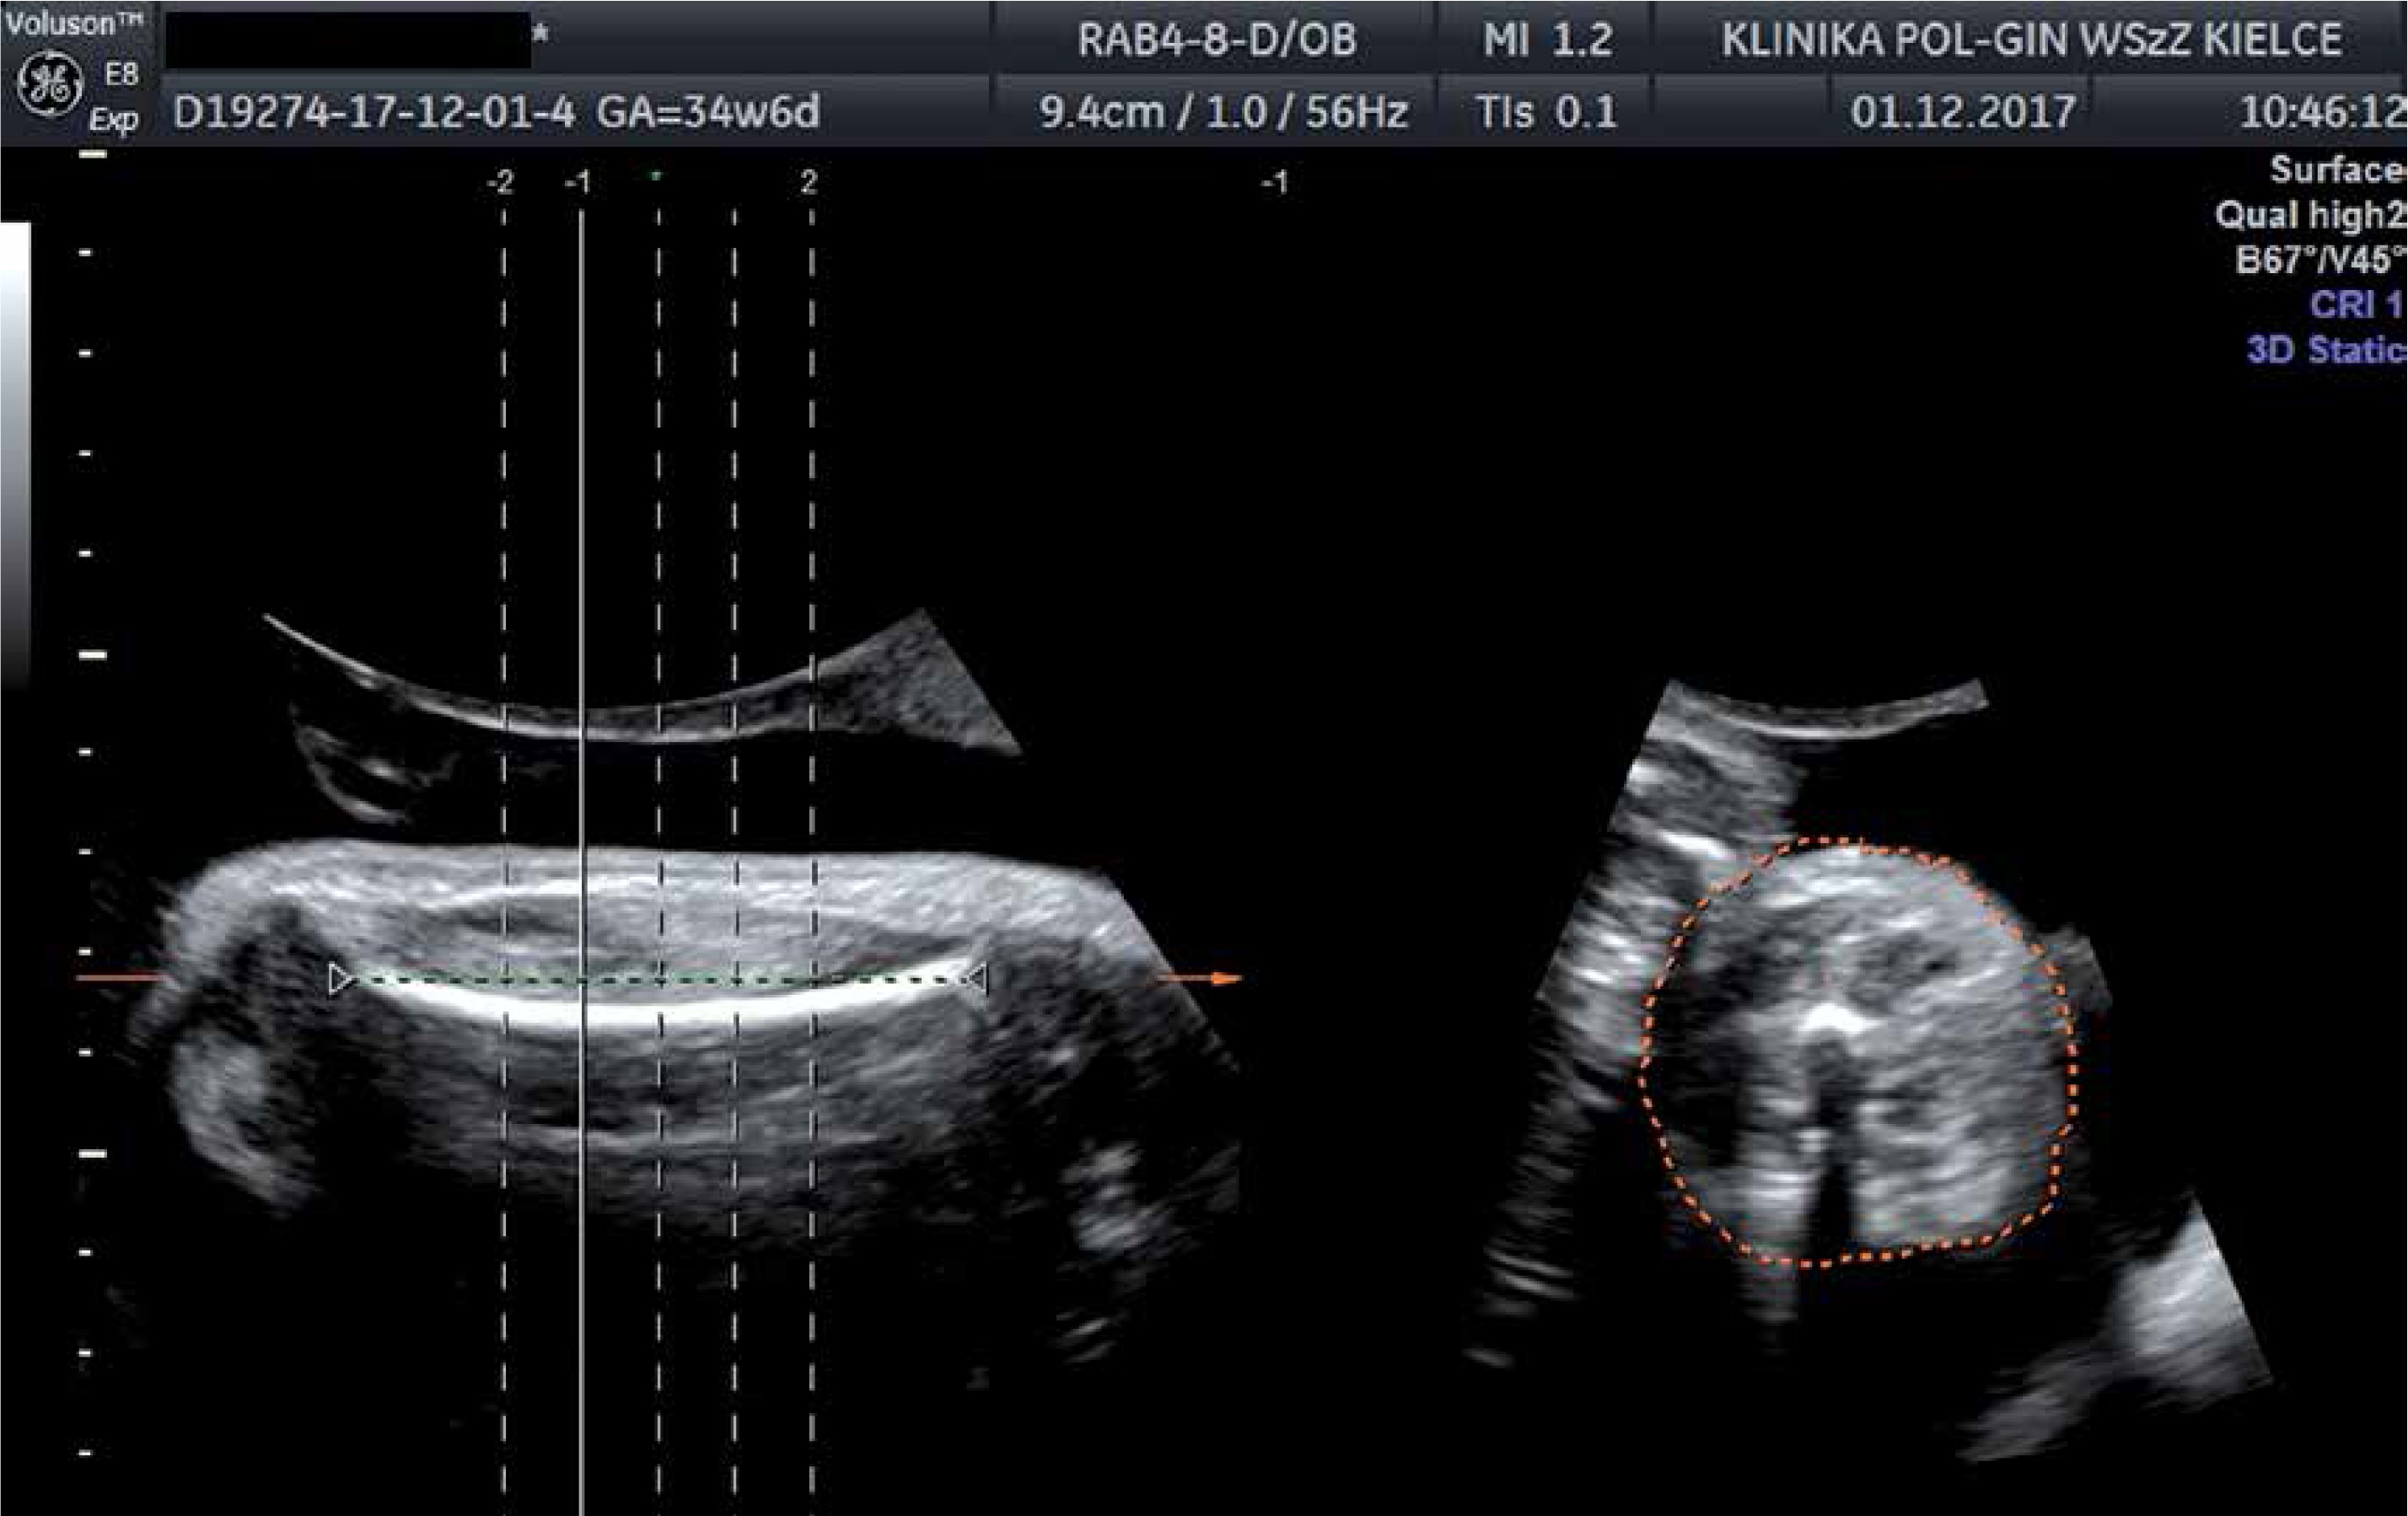

In this study we included patients in singleton, term pregnancy with cephalic presentation of the fetus. All of the patients volunteered for delivery in our clinic and consented to undergo ultrasound examination and participate in this study. Exclusion criteria were pre-labour rupture of membranes and lack of consent for participation in the study. One hundred and four singleton pregnant women met the inclusion criteria. Gestational age was between 37 and 41 (median: 39 weeks) based on the first day of the last normal menstrual period. Patients prospectively underwent three-dimensional ultrasonography for estimating TVol and two-dimensional fetal measurements with BP, HC, AC and FL taken during the same examination. Thigh volume measurement was obtained by a sagittal sweep that included both ends of the femoral diaphysis during maternal breath-holding (Figure 1). Partial volume (50% of femoral length) was automatically subdivided into five equidistant slices that were centred along the mid-thigh (Figure 2), then slices were traced manually from the transverse view of the extremity to obtain TVol (Figure 3). The Lee formula was used to calculate EFW. Evaluation took place within 3 days of delivery and was done by one certificated ultrasonographer. An independent observer measured the time taken to perform the necessary measures in 20 randomly selected patients. Amniotic fluid index (AFI) was also estimated in each patient. Women were recruited in the Department of Obstetrics and Gynaecology, Provincial Combined Hospital in Kielce. We used GE Healthcare Voluson E8 with three-dimensional curved-array abdominal transducer RAB 4–8 D and software to implement the Lee and Hadlock formulas. Immediately after delivery, neonatal staff measured BW. The percentage error (PE) between EFW and BW was calculated using the equation PE = (EFW – BW/BW) × 100%, then mean percentage errors (MPE) were calculated for each formula separately. Absolute percentage error (APE = |EFW – BW|/BW) × 100%) and median absolute percentage errors (MAPE) were calculated. We compared the MPEs and MAPEs of the formulas. We also compared the proportion of newborns with estimated BWs within ± 5% and ± 10% of actual BW. We calculated statistical measures of test performance in detecting fetal macrosomia (arbitrarily set at 4000 g) (Table I).